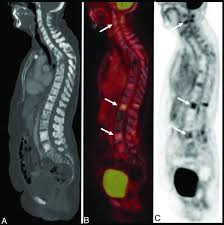

An FDG PET CT scan uses a radioactive glucose tracer (FDG) to identify areas of abnormal metabolic activity in the body. Cancer cells tend to consume more glucose than normal cells, making this scan extremely effective for early detection and disease monitoring. The Best FDG PET CT Scan in Greater Kailash helps doctors detect conditions that may not be visible on conventional imaging tests.

The Best FDG PET CT Scan in Greater Kailash is supported by advanced PET CT scanners that provide high-resolution images and precise metabolic mapping. Modern equipment ensures better detection of even small lesions, leading to early and accurate diagnosis.